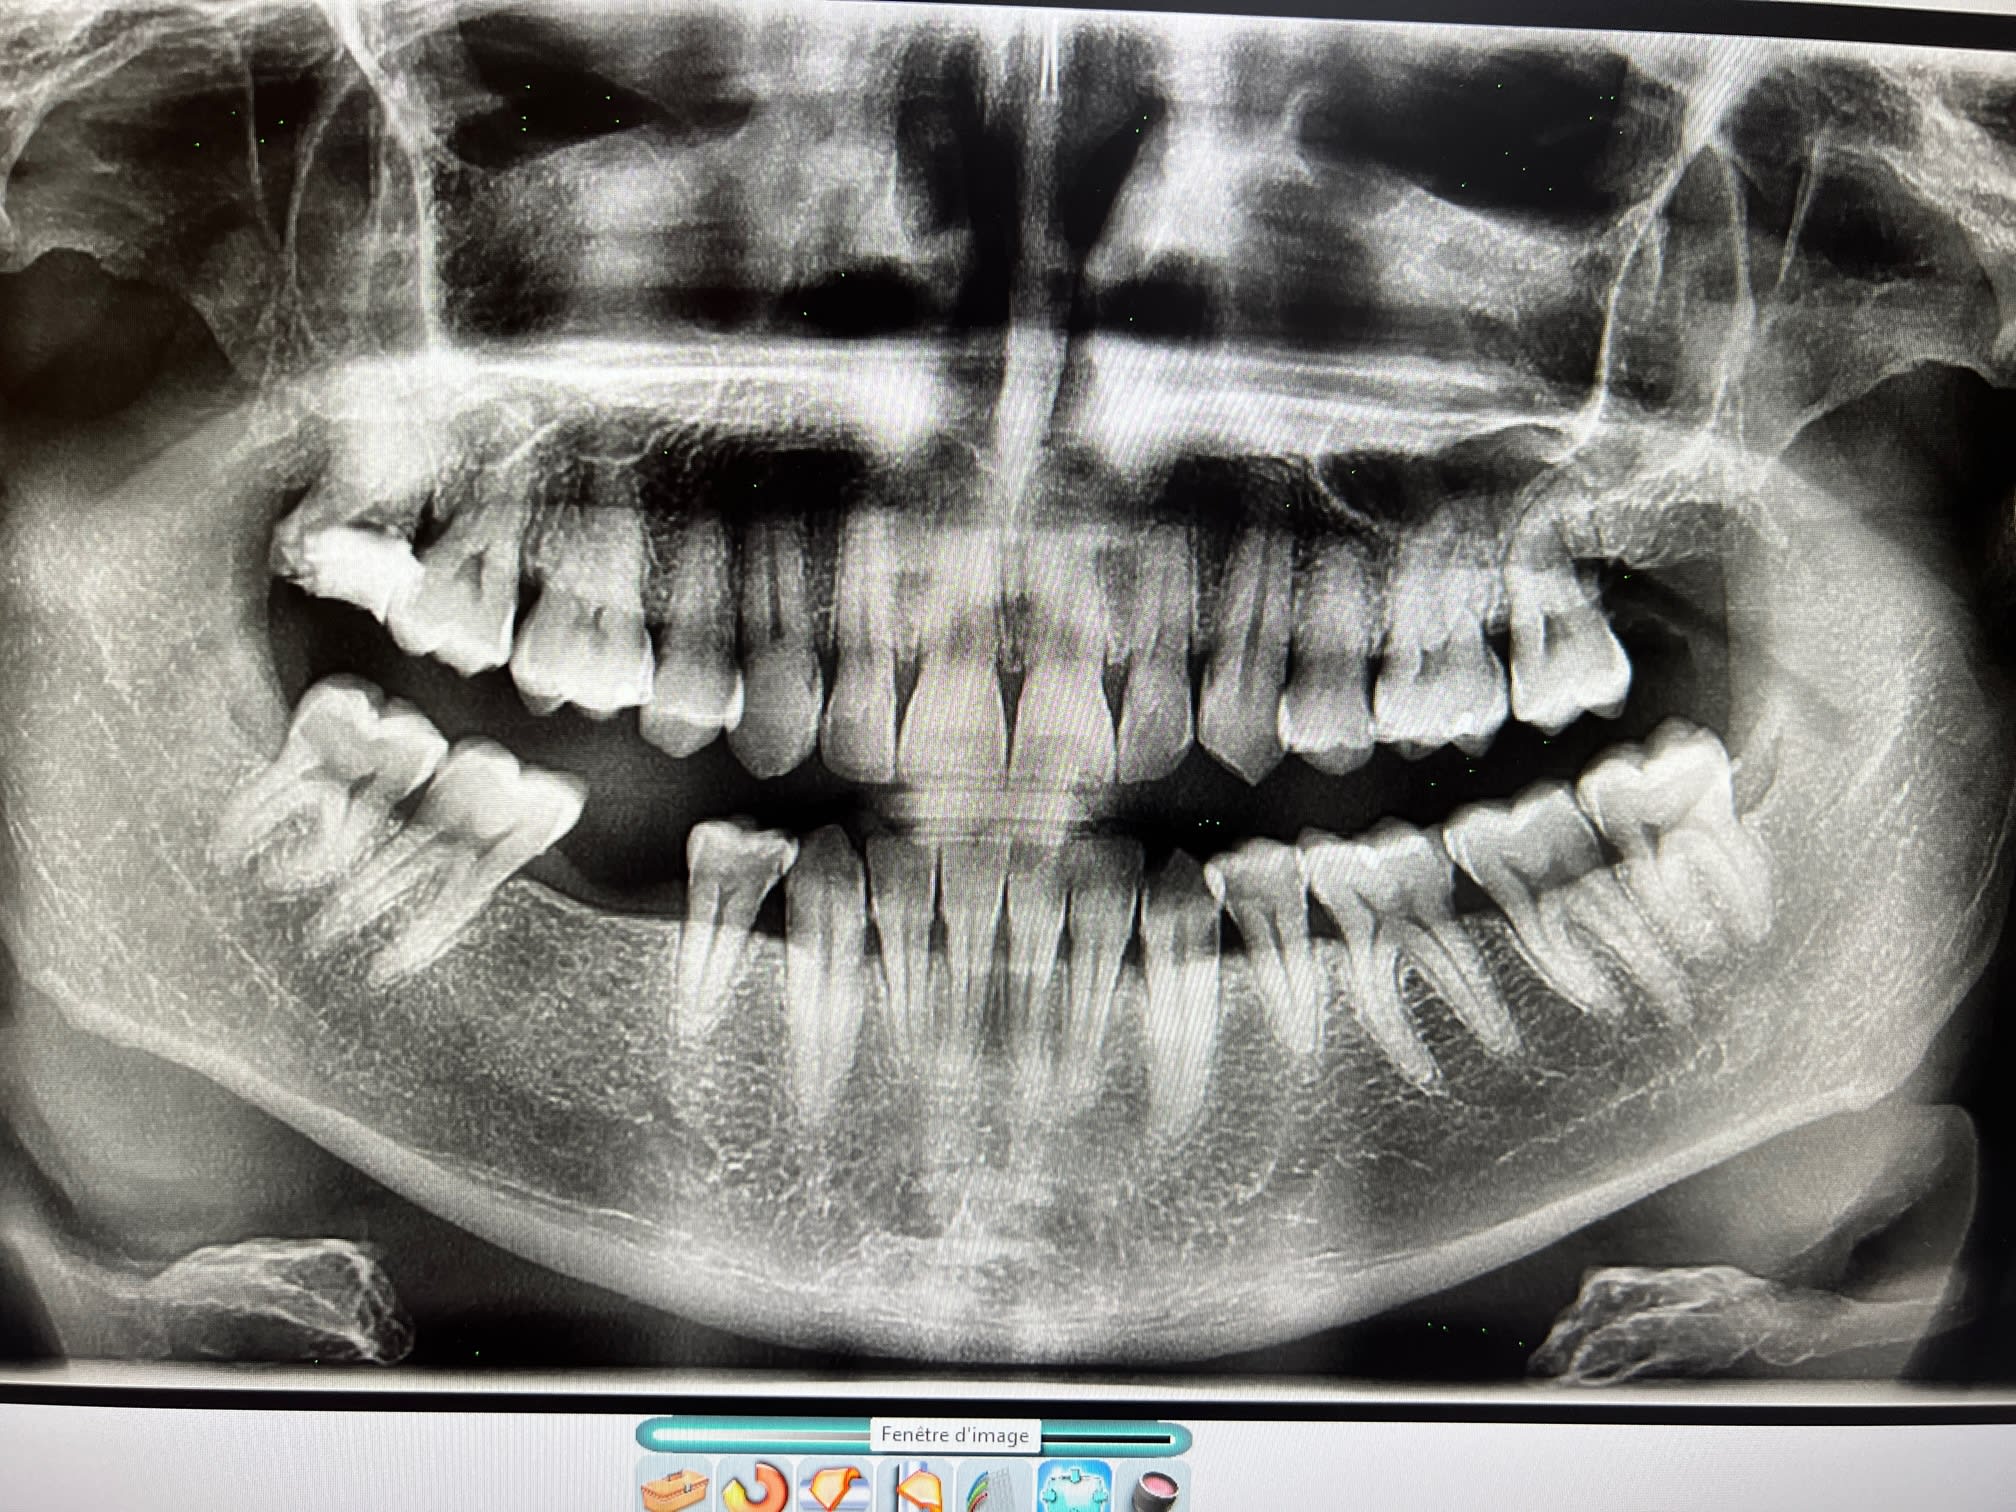

Patient adulte la 40aine, qui vient en urgence, pulpite sur la 8 maxillaire, très carie

Le problème va être la difficulté de l'extraction:

- dent carié en mésial donc pas un bon bon d'appui pour faire un effet de levier avec l'élévateur

- la dent est un peu en désinclusion, donc visible mais sous le plan d'occlusion donc pas facile d'accès, car la 7 la cache pas mal

- un os très dur (patient bruxo) donc sensation de lutter contre une dent ankylosé et donc rend la luxation difficile

- la dent a potentiellement aussi un apex courbé

la 18

La dent a été extraite, chiante comme prévu

Positionné légèrement en palatin, faible ouverture buccal, racine divergente, pas de point d'appui en mesial pour faire levier à cause de la carie, os dur (patient bruxeur)

J'ai du la couper de mesio a distal et sortir les 2 fragments qui son venu plutôt simplement ensuite